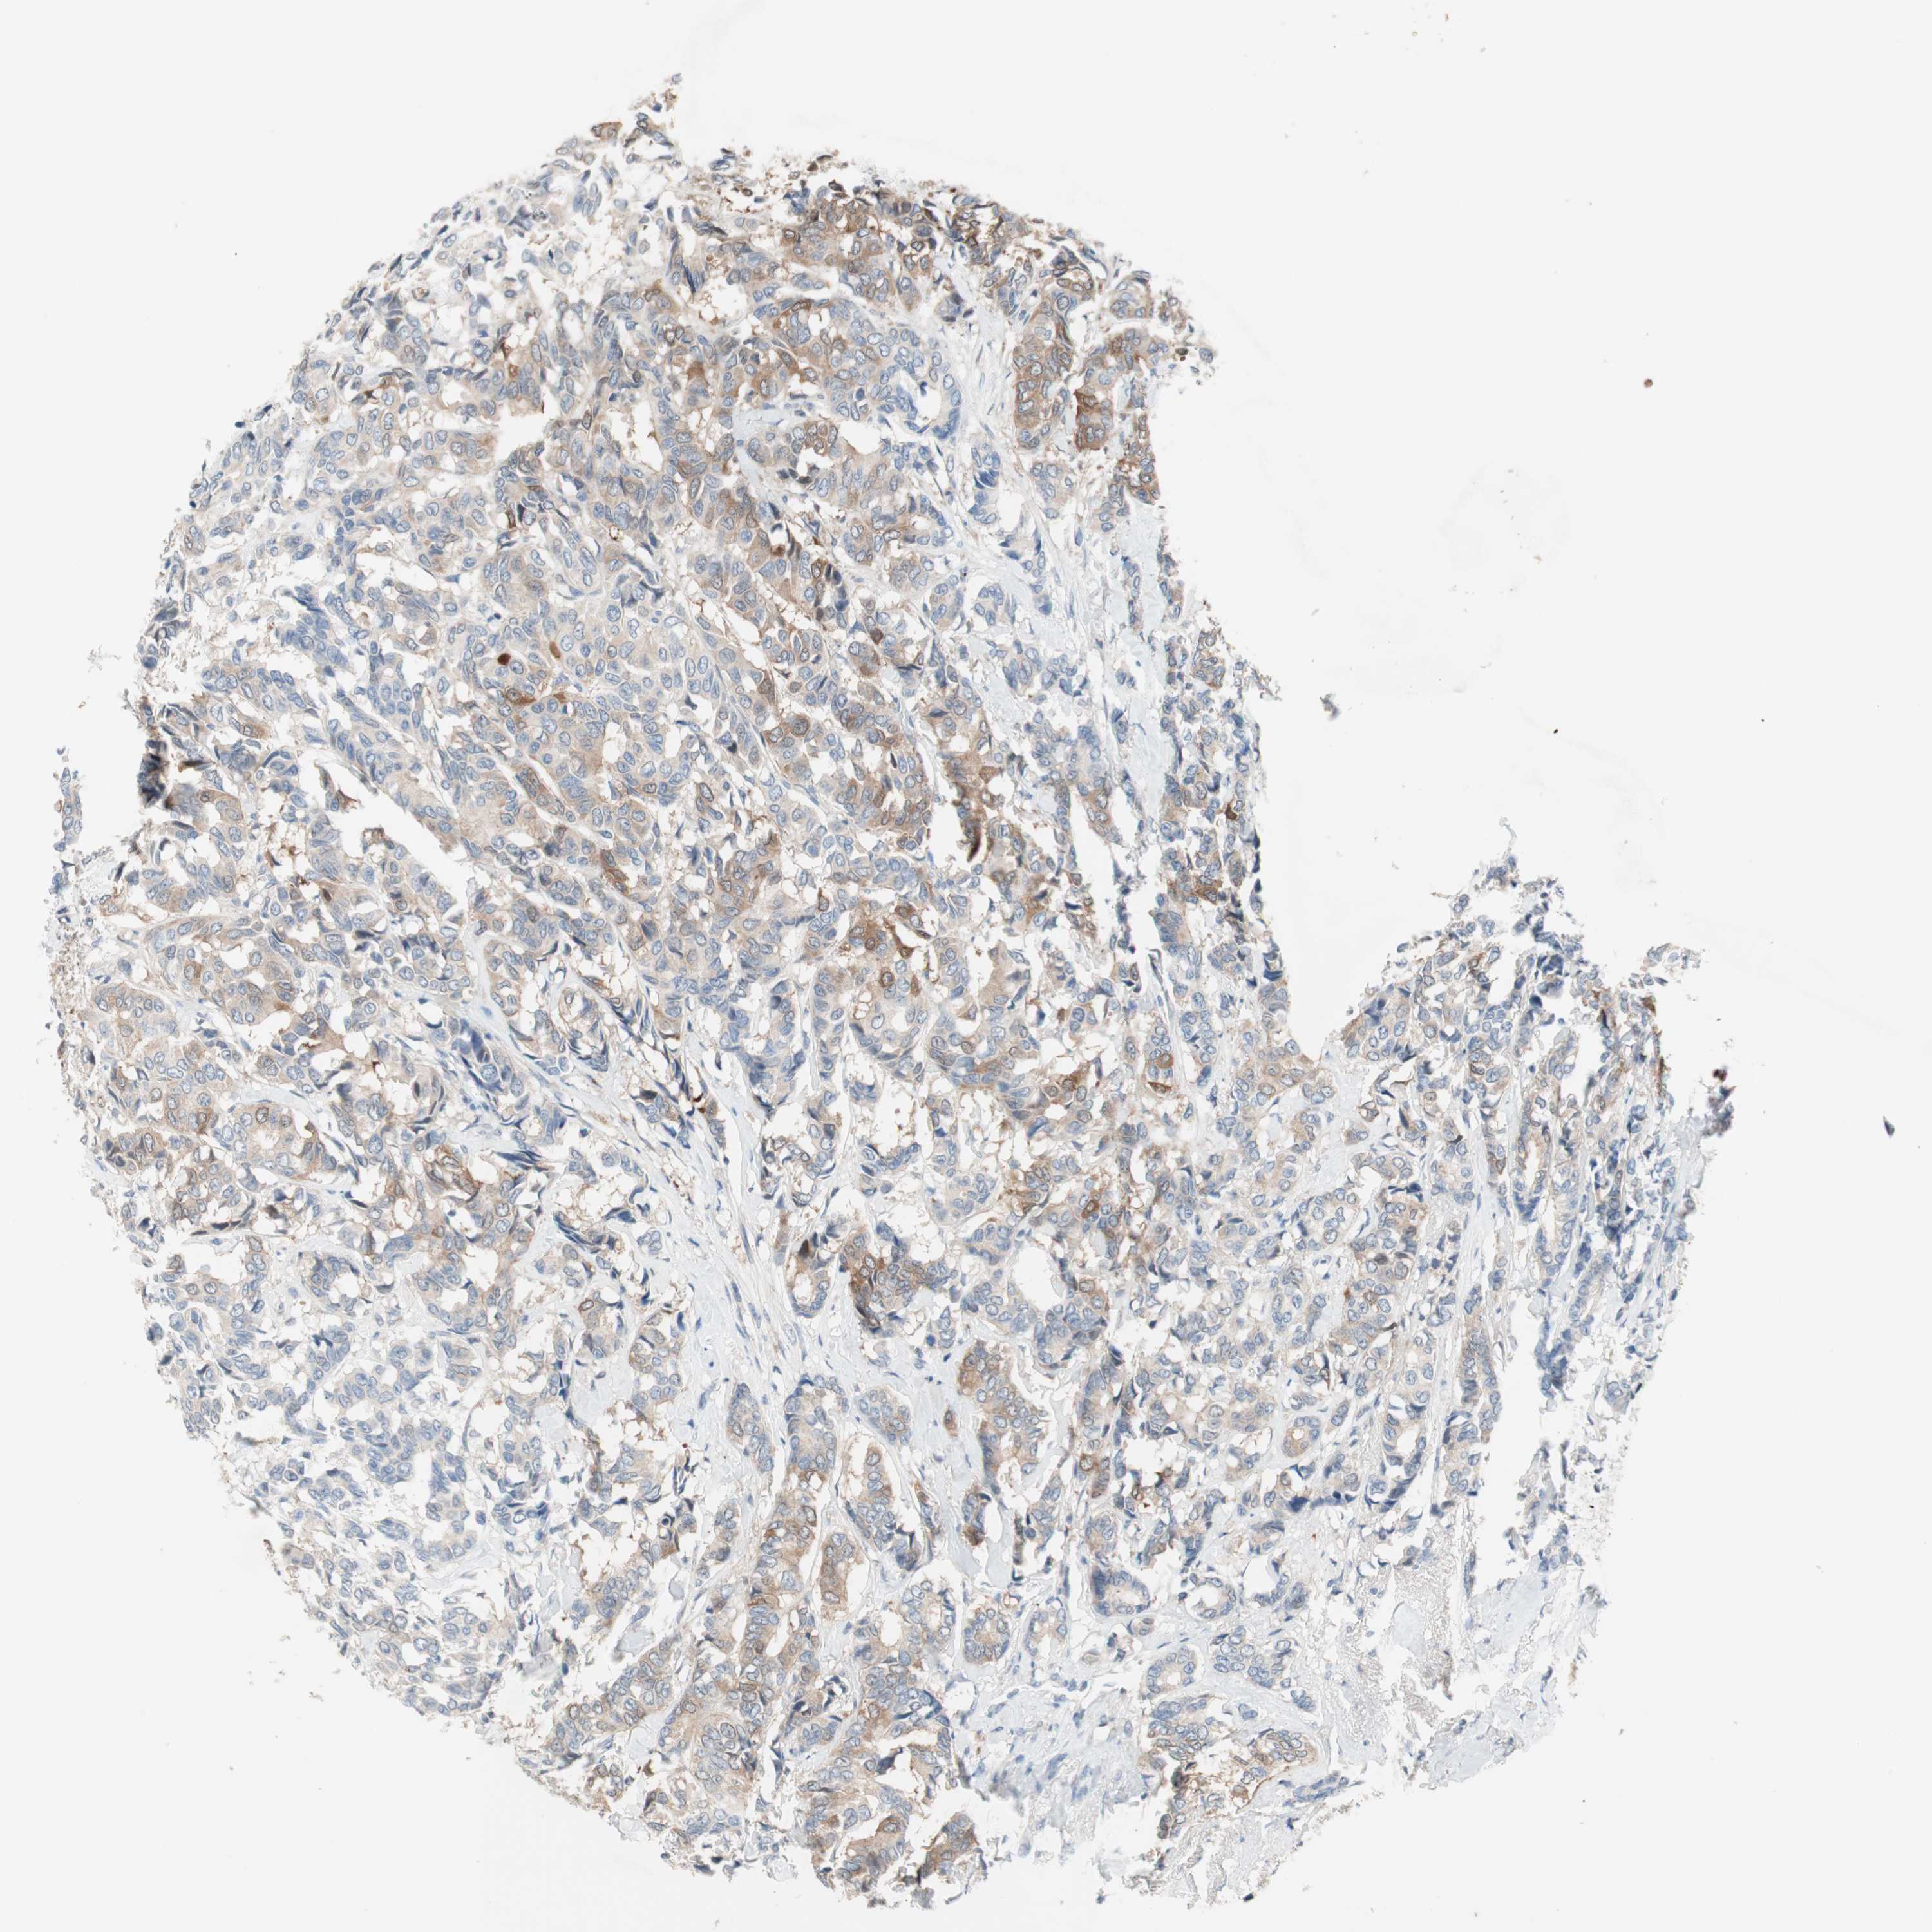

CANCER BREAST CANCER Show tissue menu

BRCA TCGA BRCA VALIDATION PROTEIN EXPRESSION